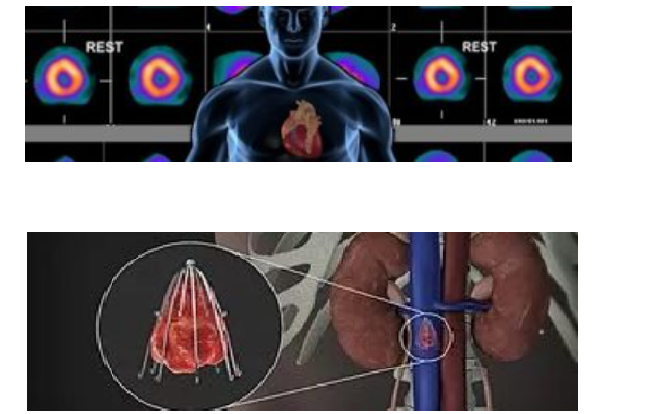

如微量核子心脏血管医学影像中心,专为胸闷丶胸痛丶心律不整丶心悸丶高血压丶高胆固醇丶糖尿病患者提供“微核心脏造影”,以确实掌握病情,并且无痛丶无副作用丶免开刀。

纽约法拉盛血管中心心脏病专科同时拥有各类先进的医疗设施:

- 运动超音波扫描;

- 彩色心脏超声;

- 颈部动脉、腹部主动脉、肾动脉和下肢动静脉超声检查;

- ABI/PVR;

- 运动平板和运动超声测心试验;

- 心电图;

- 24小时和更长时间心电监测记录供随身携带。